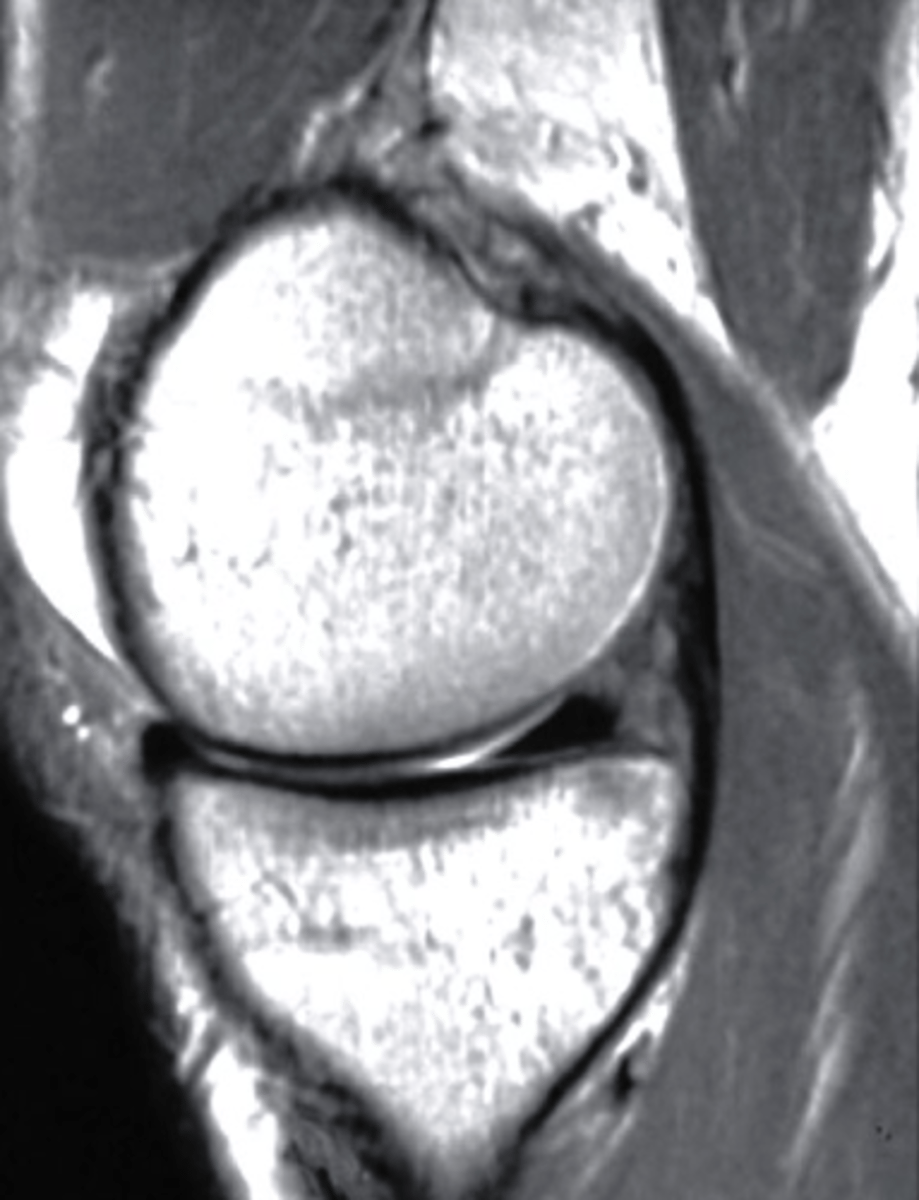

sagittal

What plane is this MRI?

a. sagittal

b. coronal

c. axial

d. AP

edema

This is an axial T2 image at the level of the femoral condyles. The open arrow points to the medial patellar retinaculum. What does the solid arrow point to?

a. Edema

b. Fatty tumor

c. Hemorrhage

d. Osteogenic tumor